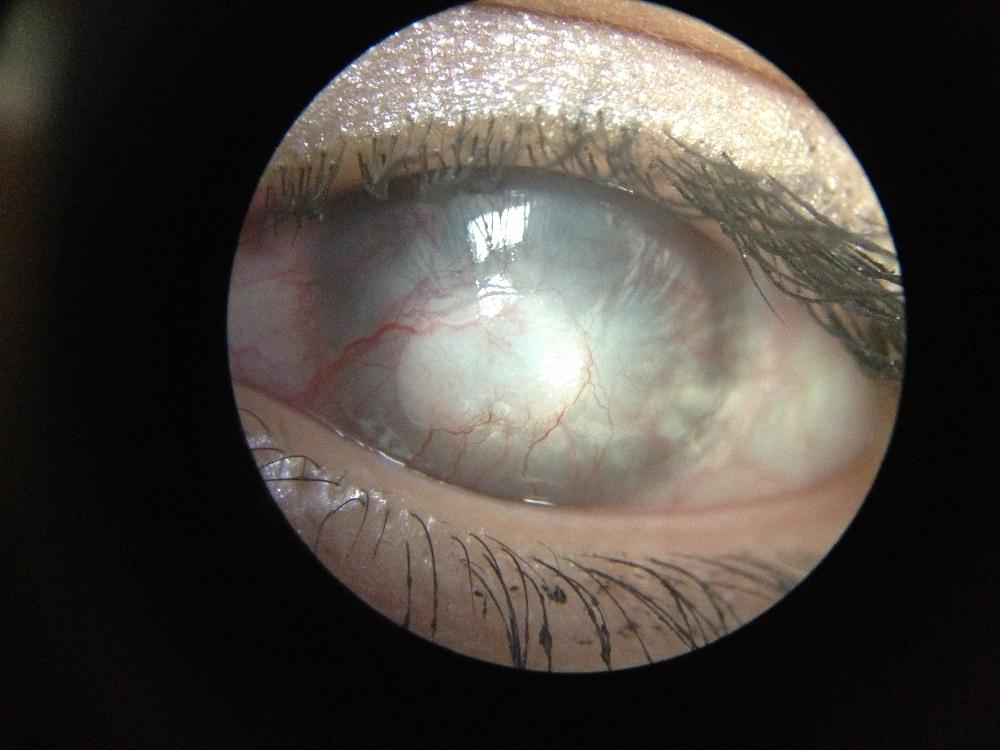

Neovascularization

Abnormal growth of new blood vessels in the cornea.

Pannus

Invasion of the peripheral cornea by infiltration and formation of the new blood vessels.